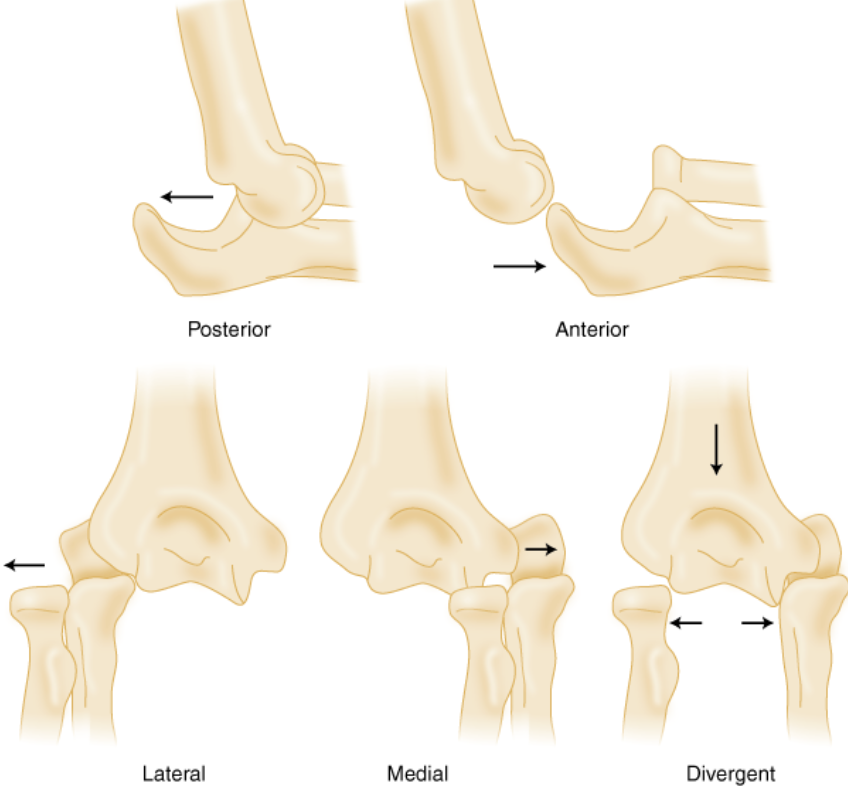

Elbow Dislocation

Displacement of elbow bones due to trauma or sports injury.